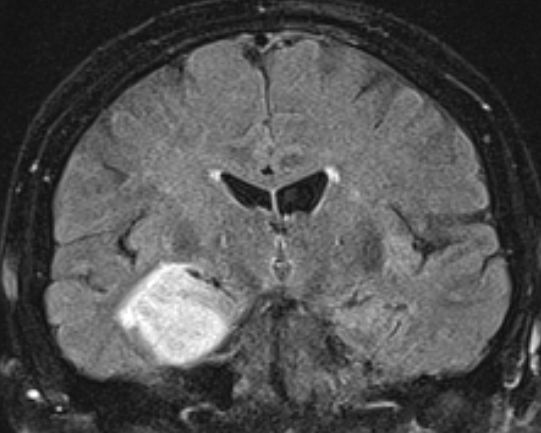

Schmetterlingsgliom des hinteren Balkens |

62-jähriger Mann mit torkeligem Gang, Amnesie und Verwirrtheit. Schmetterlingsgliom des hinteren Balkens.![]() |

![]() |

![]() | |